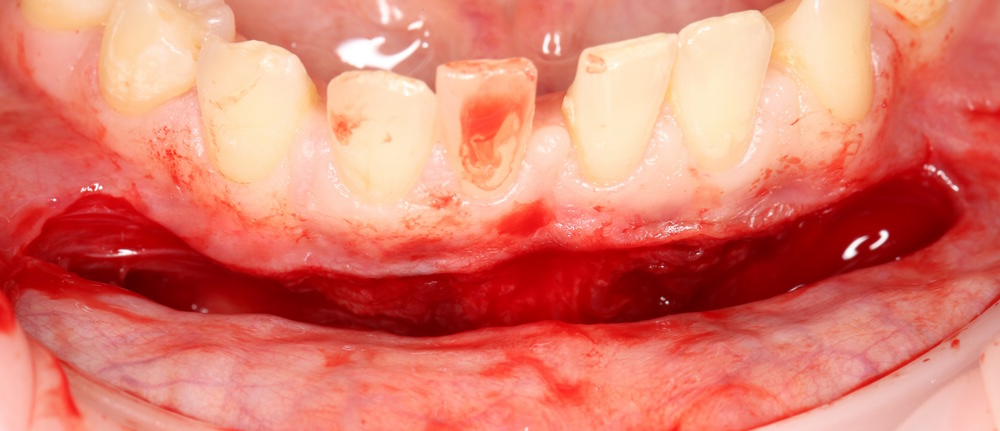

Разрез в преддверии полости рта, на 1-2 мм ниже переходной складки:

Тупым способом отслаиваются мягкие ткани до надкостницы. Ее очень легко определить — она, в отличие от других слоев, она неподвижно прикреплена к кости. Таким образом, создается ложе под матрицу Mucograft:

Следует учесть, что в процессе рубцевания рана немного стянется.

Поэтому, отслойка и сепарация тканей делается с небольшим запасом.